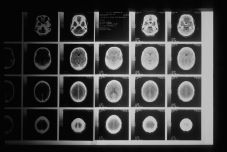

agyi képalkotás